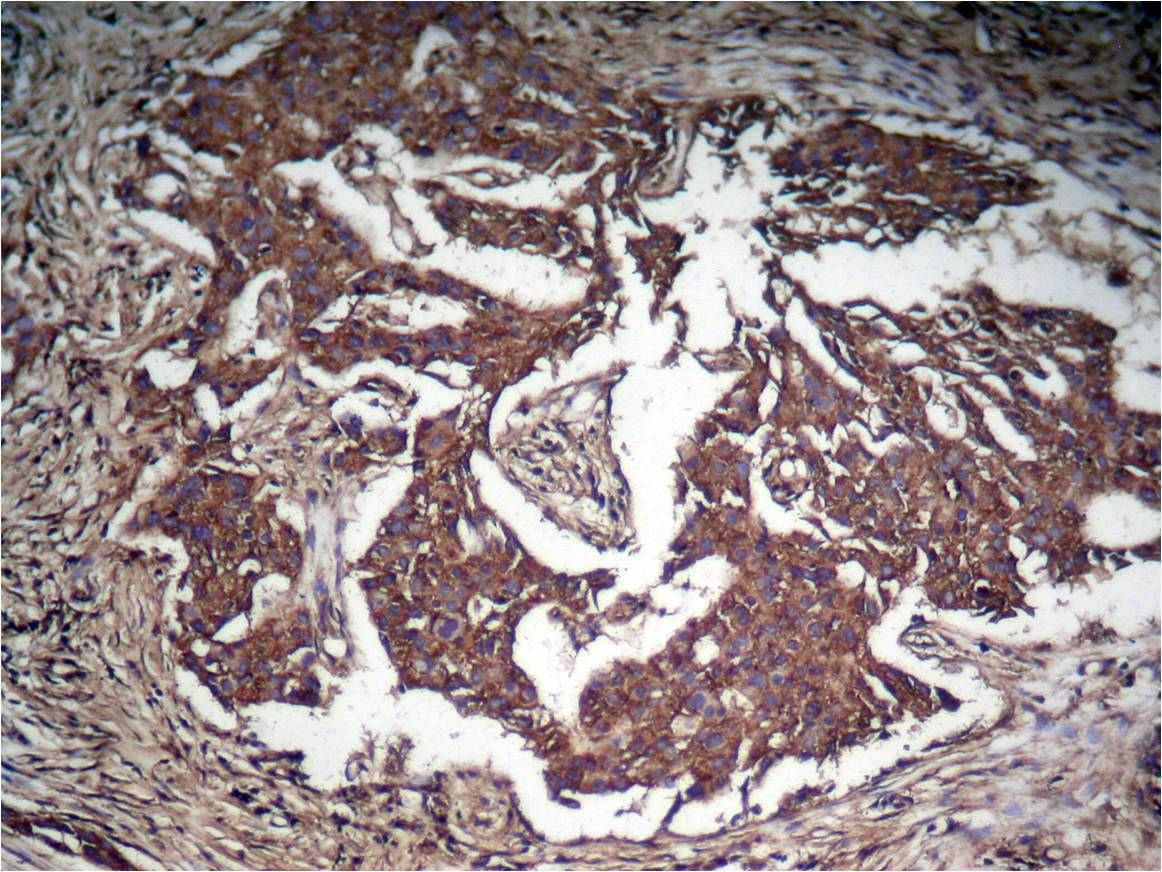

分类: 科研抗体货号: P40045别名: APRF; Acute-phase response factor; HIES应用: WB,IHC,IF反应种属: Human,Mouse,Rat